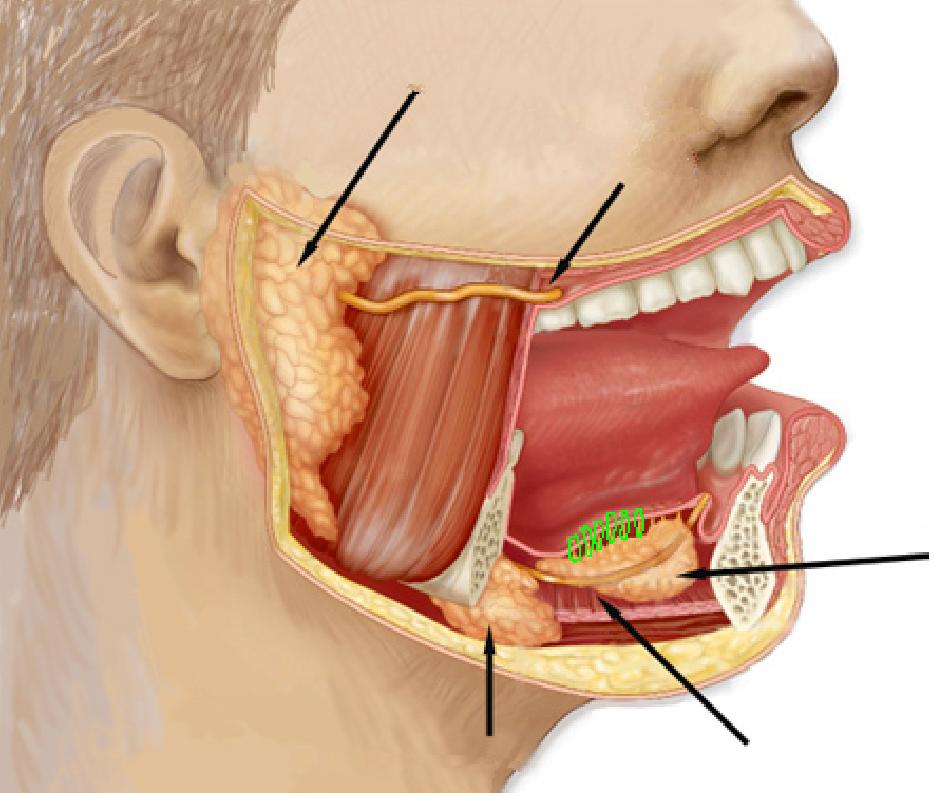

Genioglossus

Hyoglossus

Palatoglossus

Styloglossus

Parotid gland

Parotid duct

Submandibular gland

Submandibular ducts

Sublingual gland

Sublingual ducts